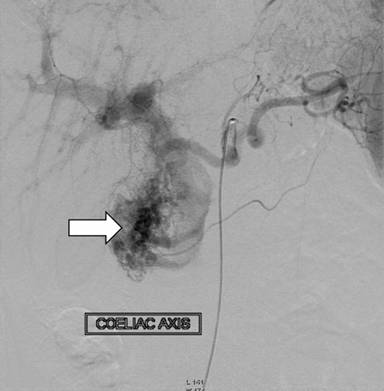

The patient had recurrence of upper gastrointestinal bleeding three days after the endoscopic intervention, requiring transfusion of two more units of packed red blood cells. He was taken up for emergency endoscopy which revealed bleeding ulcer in the proximal duodenum and a repeat session of injection sclerotherapy was done; however, the bleeding did not stop. In view of continuing bleeding, the patient underwent conventional angiography which revealed a diffuse vascular blush in the head of the pancreas (Figures 4 and 5) with early filling of the veins suggestive of tumor blush. Feeder from the gastroduodenal artery was embolized with gelfoam and coil. Check angiography showed no early filling of veins. Superior mesentery artery angiogram showed similar blush in the same region but could not be embolized.

Figure 4. Selective celiac axis angiography showing vascular blush. |